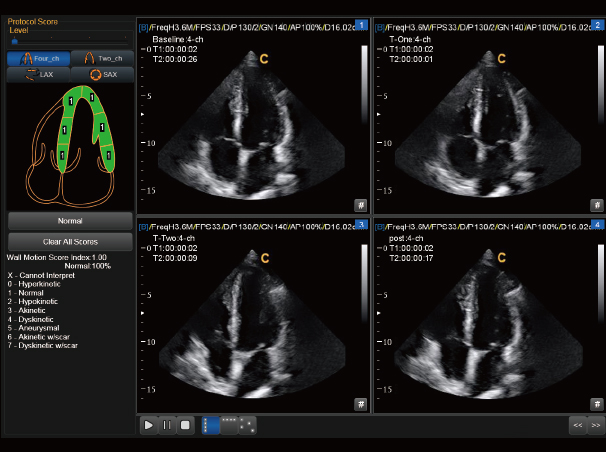

负荷心超